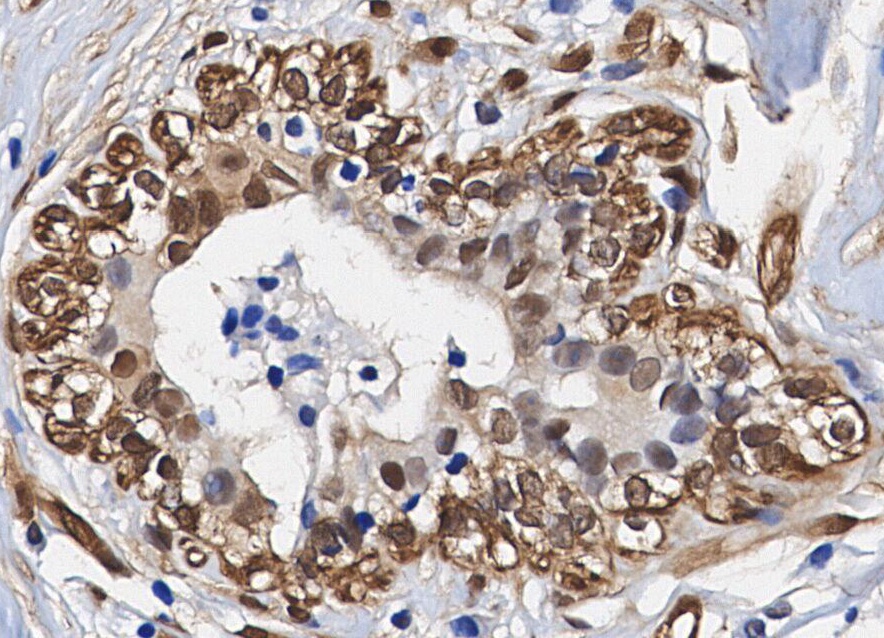

• Immunohistochemical analysis of formalin fixed paraffin embedded human Breast Cancer tissue with F1116 at 1/100 dilution.